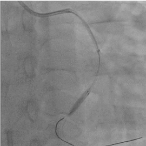

Trans-radial coronary angiogram revealed tortuous and aneurysmal dilatation (ectatic vessels) of all three major coronary arteries (Figure 3a, 3b) with huge thrombus in the proximal segment of left circumflex (LCx) artery, the culprit lesion was identified. Left coronary system was engaged with XB 3.0 6-French guiding catheter through right radial access with 6F sheath. The lesion was crossed by Run through NS floppy (Terumo) hydrophilic 0.014 inches wire. Among different strategies to deal with huge thrombus burden such as Plain Old Balloon Angioplasty (POBA), thrombus aspiration and intracoronary glycoprotein IIb/IIIa inhibitor, we proceeded with thrombus aspiration. Thrombuster II (Kaneka Corporation) thrombus aspiration catheter introduced into the target vessel and suctioning performed. Blood clots aspirated as shown (Figure 4). After few aspirations, failed to do further suctioning and planned to flush as the catheter may get blocked from aspirated thrombus. Some degree of resistance was felt while removing the catheter from the vessel. The thrombus aspiration catheter finally came out with slight pulling force but noted that the tip was missing (Figure 5). Angiographically, the tip of Thrombuster II catheter seen attached to the guidewire (Figure 6). The guidewire can move freely along the mid and distal LCx but failed to withdrawal at the proximal LCx area.

Figure 3a. Left coronary artery Figure 3b. Right coronary artery